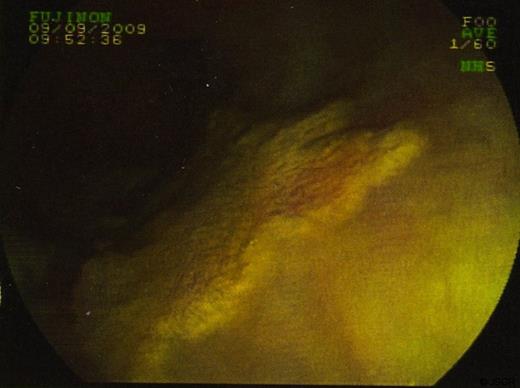

In September 2009 the patient underwent a colonoscopy and oesophagogastroduodenoscopy (OGD). Colonoscopy was unremarkable. However, views of the oesophagus on OGD showed what was thought to be a superficially spreading tumour, 35cm from the incisors and 5 cms in length. Barrett’s oesophagus was also seen. (figure 1 & 2)